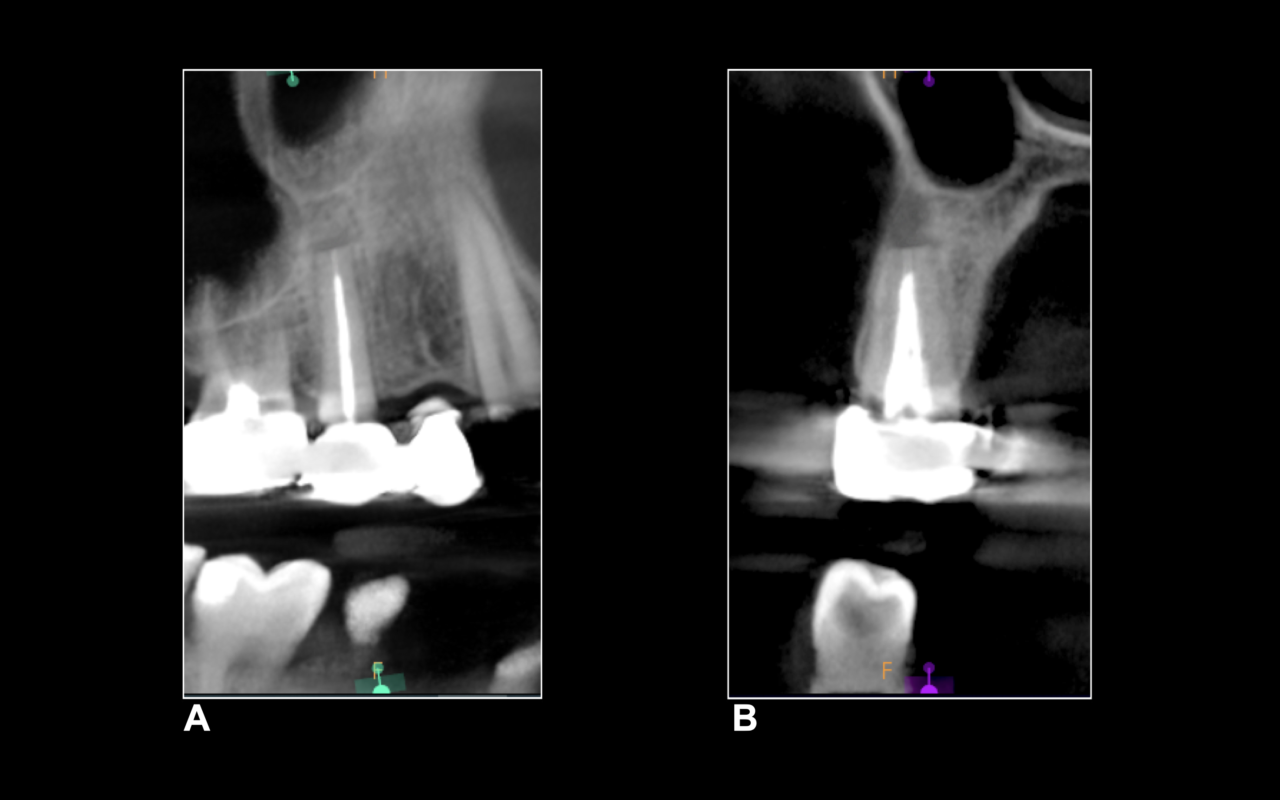

Attraverso la CBCT (Figura 2a) è possibile calcolare con precisione la posizione dell’apice radicolare. La breccia ossea e il taglio dell’apice radicolare (Figura 2b) sono eseguiti in modo conservativo. Dopo l’apicectomia, ad alto ingrandimento 24x e utilizzando un micro-specchietto è possibile notare l’area bianca centrale completamente calcificata (Figura 2c).

A distanza di otto mesi dall’intervento, si esegue un controllo radiografico 3D per valutare la reale guarigione dell’elemento 1.5. La CBCT evidenzia la riformazione della corticale vestibolare a livello apicale e la scomparsa della lesione periapicale (Figure 7a-b).